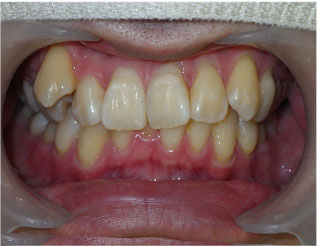

この方は上下の歯並びが全体的に悪い状態でした。

クリアコレクト矯正というマウスピース矯正で治しました。

期間は2年でした。